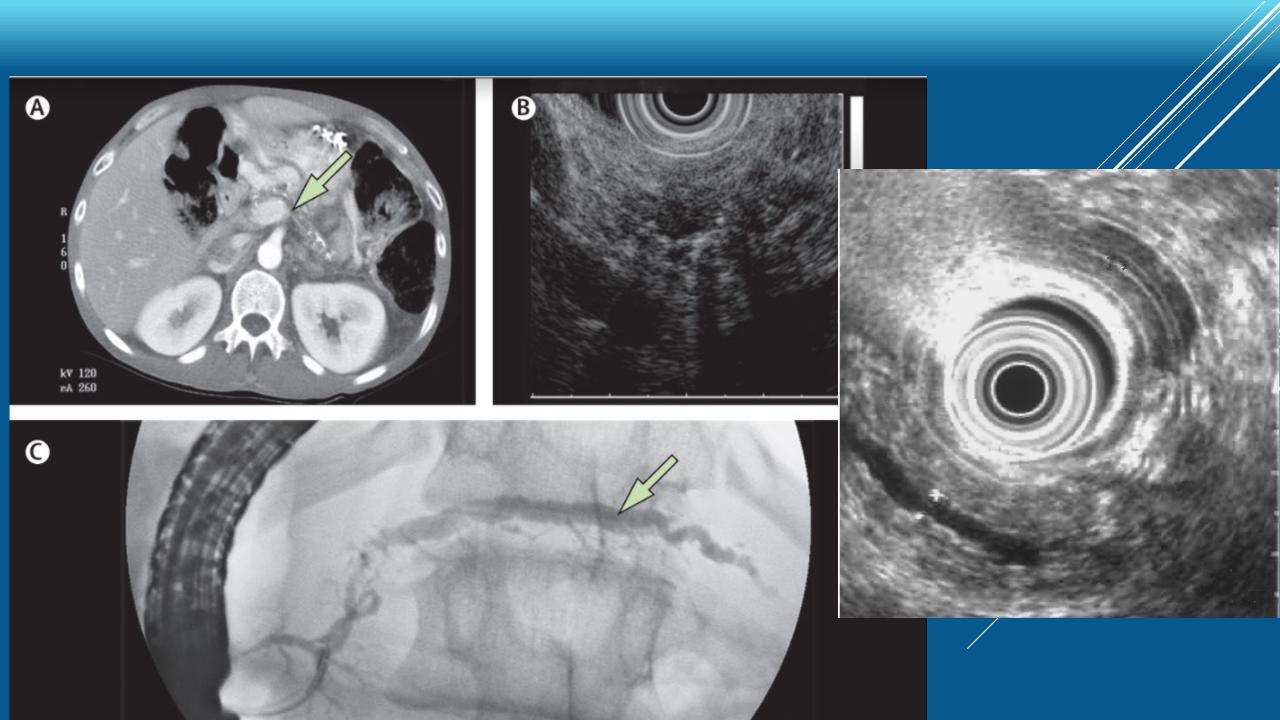

УЗ- и КТдиагностика хронического панкреатита

Хронический панкреатит: диагностика

Хронический панкреатит: УЗ-критерии

Главные критерии:

А. Гиперэхогенные очаги длиной и шириной ≥2 мм с тенью. А. Панкреатолитиаз

B. Отграниченные ячеистые структуры с наличием ≥3 смежных долек

Дополнительные критерии:

Кисты

Расширение панкреатического протока >3,5 мм

Неровные контуры панкреатического протока

Расширение боковых ветвей панкреатического протока >1 мм

Гипоэхогенность стенок панкреатического протока

Наличие фиброзных тяжей

Гиперэхогенные очаги без тени

Дольчатость без наличия смежных долек

Определенный ХП: 1 главный А-критерий + 3 дополнительных критерия или 1 главный А-критерий + 1 главный B-критерий или 2 главных А-критерия Вероятный ХП: 1 главный А-критерий или 1 главный B-критерий + 3 дополнительных критерия или 5 дополнительных критериев Неопределенный ХП: 3-4 дополнительных критерия или 1 главный В-критерий